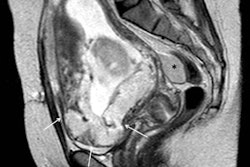

Sagittal T1-weighted volume interpolated gradient-echo MR image evidences focal hyperintense signal intensity of the placenta, compatible with recent hemorrhages."The combination of these four imaging features shows a stepwise multiple regression coefficient of 0.36. Our data suggest that this 'gold combination' increases the specificity of MRI and may enable a reliable detection of placental implantation disorders," they wrote.